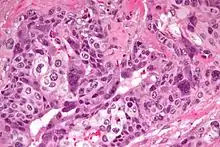

Micrograph of choriocarcinoma showing both of the components necessary for the diagnosis - cytotrophoblasts and syncytiotrophoblasts. The syncytiotrophoblasts are multinucleated and have a dark staining cytoplasm. The cytotrophoblasts are mononuclear and have a pale staining cytoplasm. H&E stain. | |

Characteristic feature is the identification of intimately related syncytiotrophoblasts and cytotrophoblasts without formation of definite placental type villi. Since choriocarcinomas include syncytiotrophoblasts (beta-HCG producing cells), they cause elevated blood levels of beta-human chorionic gonadotropin.

Syncytiotrophoblasts are large multi-nucleated cells with eosinophilic cytoplasm. They often surround the cytotrophoblasts, reminiscent of their normal anatomical relationship in chorionic villi. Cytotrophoblasts are polyhedral, mononuclear cells with hyperchromatic nuclei and a clear or pale cytoplasm. Extensive hemorrhage is a common finding.